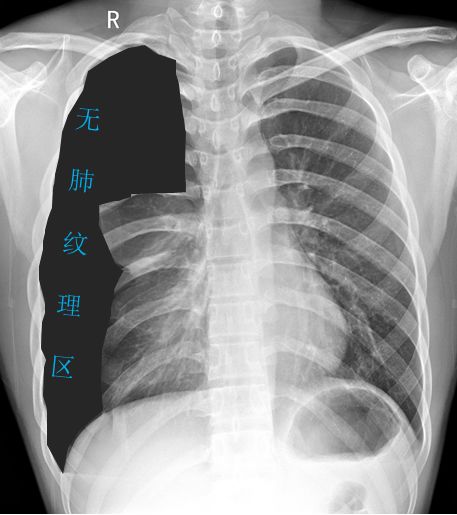

-

黑色区域:无肺纹理区域。肺叶压缩约70%;

蓝色虚线:被压缩肺组织边缘;

紫色箭头:肋膈角可见液-气平面;

橙色实线:第3、4肋骨前端骨桥关节,肋骨骨桥(先天变异);

可见心影及纵隔向对侧轻度移位。